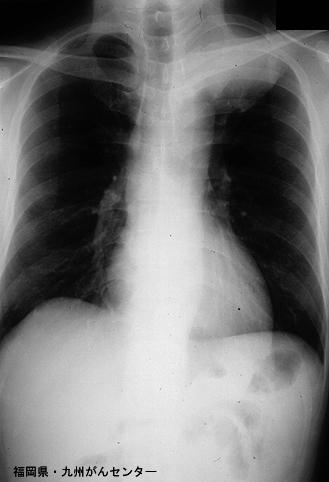

Tumor metastásico del Intestino Delgado a partir de Cáncer a células gigantes del Pulmón descubierto por melena como síntoma principal (Caso presentado por el Centro del Cáncer del Hospital Nacional de Kyushu)

Fukuoka Pref., Centro Kyushu de Curaciones de Cáncer

[Image-ID:3997]

Tumor de tipo Metastásico/

parte(separada por órganos)

mas de dos órganos/

método de exámen

Rayos X

diámetro mayor del tumor

40 -